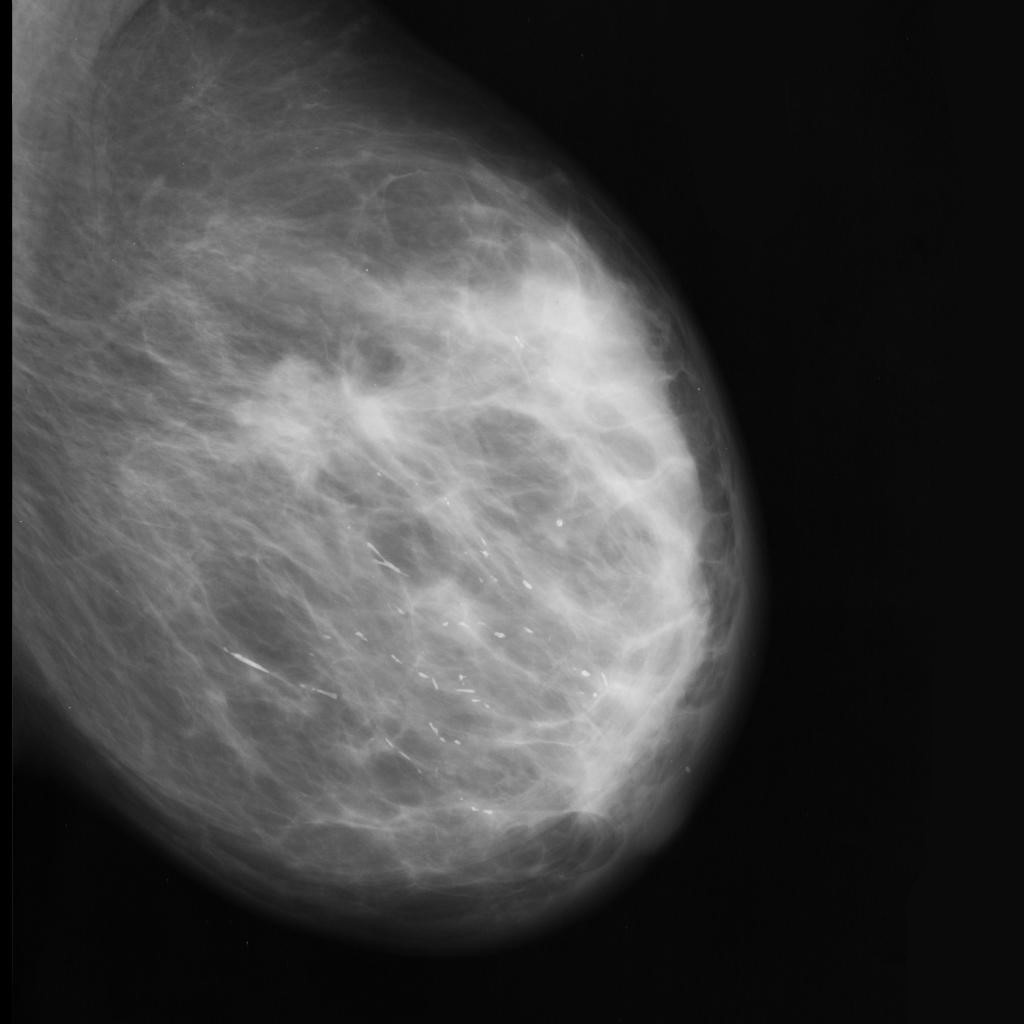

malignant